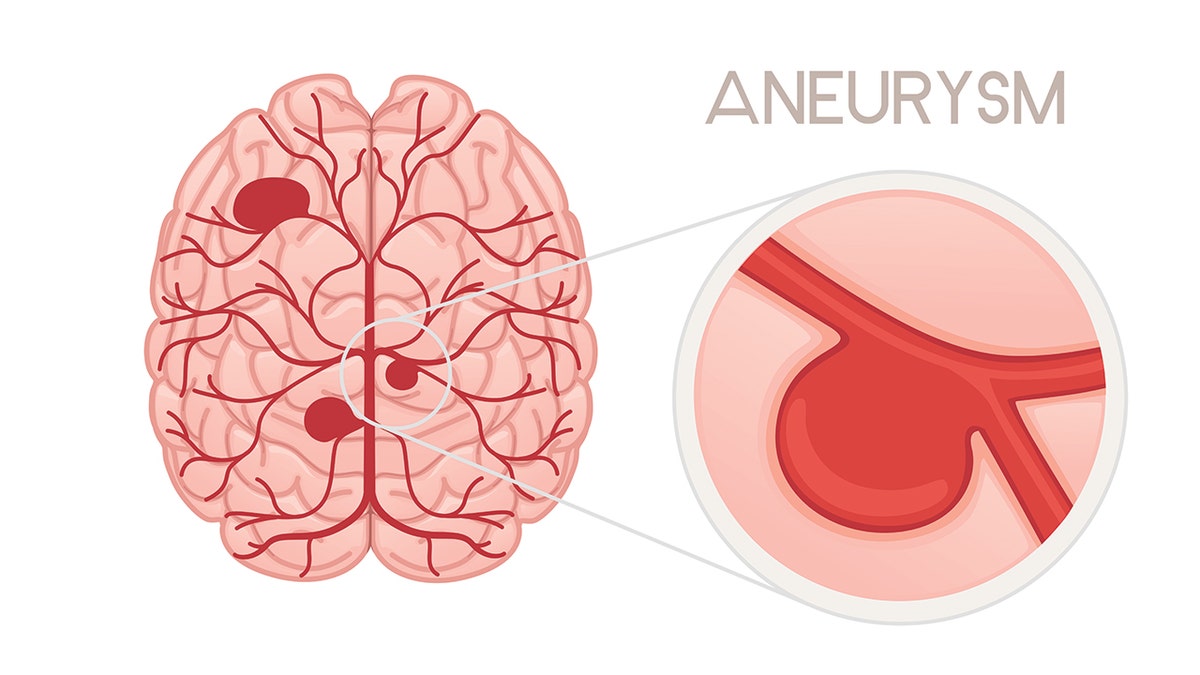

A brain aneurysm is the ballooning of a blood vessel in the brain, which can leak or rupture, leading to bleeding, according to Mayo Clinic.

Dr. Adam Arthur, chairman of neurosurgery at the University of Tennessee, described an aneurysm as a weakness on the wall of an artery, like a little water balloon that forms off a hose.

This is known as a hemorrhagic stroke, which can be life-altering and even fatal. Most aneurysms are small and not serious if they don’t rupture.

Up to one in 50 people have a brain aneurysm, which is the ballooning of an artery in the brain. (iStock)